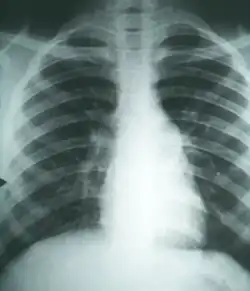

Imaging

Chest X-rays rarely demonstrate lung nodules or cavities. These images commonly demonstrate lung opacification, pleural effusions, or enlargement of lymph nodes associated with the lungs.[4] Computed tomography scans of the chest are more sensitive than chest X-rays to detect these changes.[4]